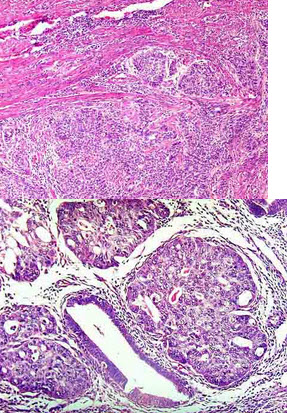

女性,58岁,绝经后阴道不规则出血,行子宫切除手术,显微镜下见腺体结构少,实性巢状区占肿瘤部分70%,细胞异型性明显,核分裂像易见(如图)。应诊断为()

A .子宫内膜腺癌Ⅰ级

B .子宫内膜腺癌Ⅱ级

C .子宫内膜腺癌Ⅲ级